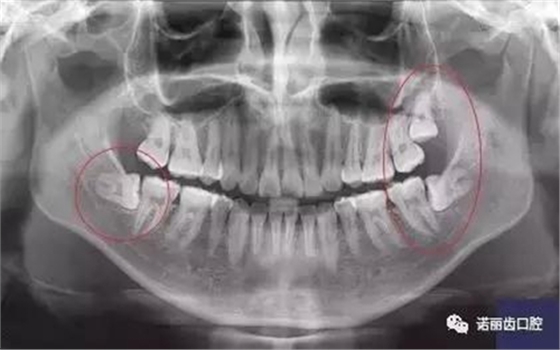

那么,如何判斷自己的智齒生長(zhǎng)情況呢?除了有明顯的疼痛感你需要做相應(yīng)的處理,同時(shí)通過(guò)X線可以觀察智齒的數(shù)量和位置以及具體情況。

經(jīng)過(guò)拍片探查,確定了以下情況的,那么,果斷的,禍患不可留啊: